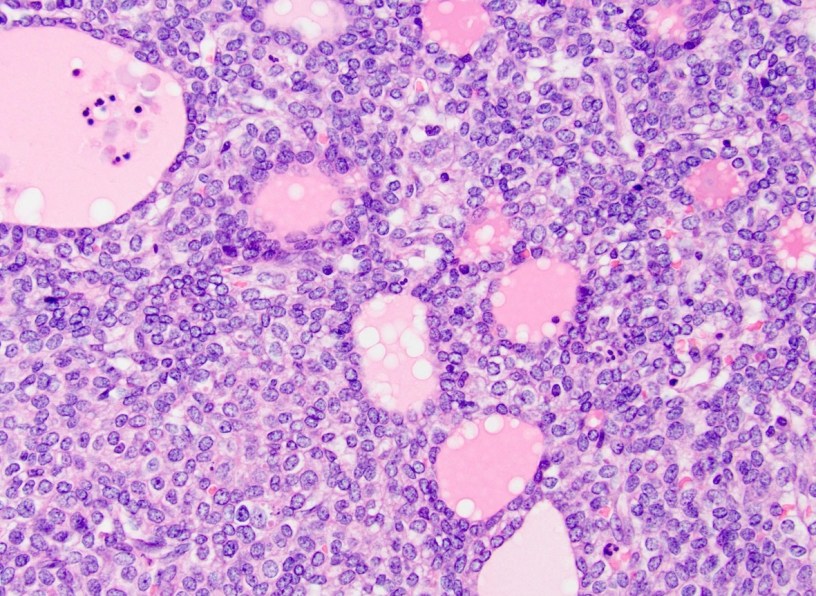

Il colangiocarcinoma è un tumore raro del fegato che colpisce ogni anno circa 5.500 persone in Italia. Il cancro emerge da una trasformazione maligna dei colangiociti, le cellule che rivestono le vie biliari. Purtroppo la diagnosi della malattia avviene spesso in fase avanzata, perché questo tipo di tumore dà pochi segni della sua presenza. Anche per questo motivo il trattamento è difficile: al momento della diagnosi solo il 10-30 per cento dei pazienti ha un tumore operabile chirurgicamente. «Proprio per le ridotte opzioni terapeutiche e l’alta mortalità del colangiocarcinoma, abbiamo bisogno di nuovi modelli di laboratorio in grado di riprodurre le caratteristiche della malattia», spiega Lleo De Nalda. «Da questo punto di vista è particolarmente importante l’interazione tra le cellule del tumore e quelle del sistema immunitario, che svolgono un ruolo fondamentale nella progressione e nella risposta ai farmaci».

All’interno del dispositivo, nei canali micrometrici scavati grazie ad avanzate tecniche fotolitografiche, i ricercatori hanno “seminato” le cellule prelevate da pazienti con colangiocarcinoma, lasciando che riproducessero l’architettura del tumore. In una serie di esperimenti hanno dimostrato le potenzialità del dispositivo nel ricapitolare il più fedelmente possibile quanto avviene nei pazienti a livello individuale, sia in termini di attivazione delle cellule T, che risulta associata all’infiltrazione del tumore, sia in termini di risposta terapeutica a diversi farmaci, che corrisponde alle caratteristiche della recidiva.